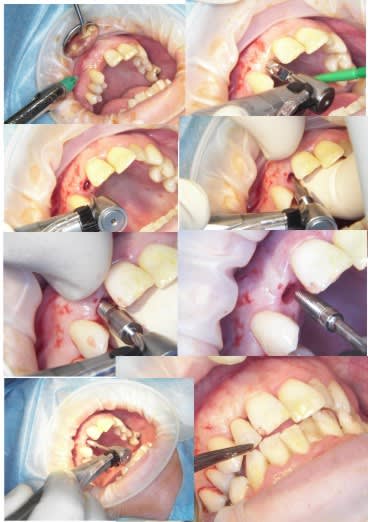

j'ai fait une bonne matinée implanto ce matin avec mélange des techniques 2 Summers avec un mélange expanseurs/condenseurs Meissinger, ostéotomes impactés pour la corticale qui faisait de la résistance, eponge pour la membrane, puis une reprise d'echec sur une mise en vitrine immédiate (fracture en mangeant une frite calcinée, à un mois!le 14/07)déposé le 15/07 mais avec mouvements pendant 24 heure et de 3.4mm j'ai du passer à 5.2!

les photos d'hier avec la mise en vitrine immediate et la reprise

--

xbk